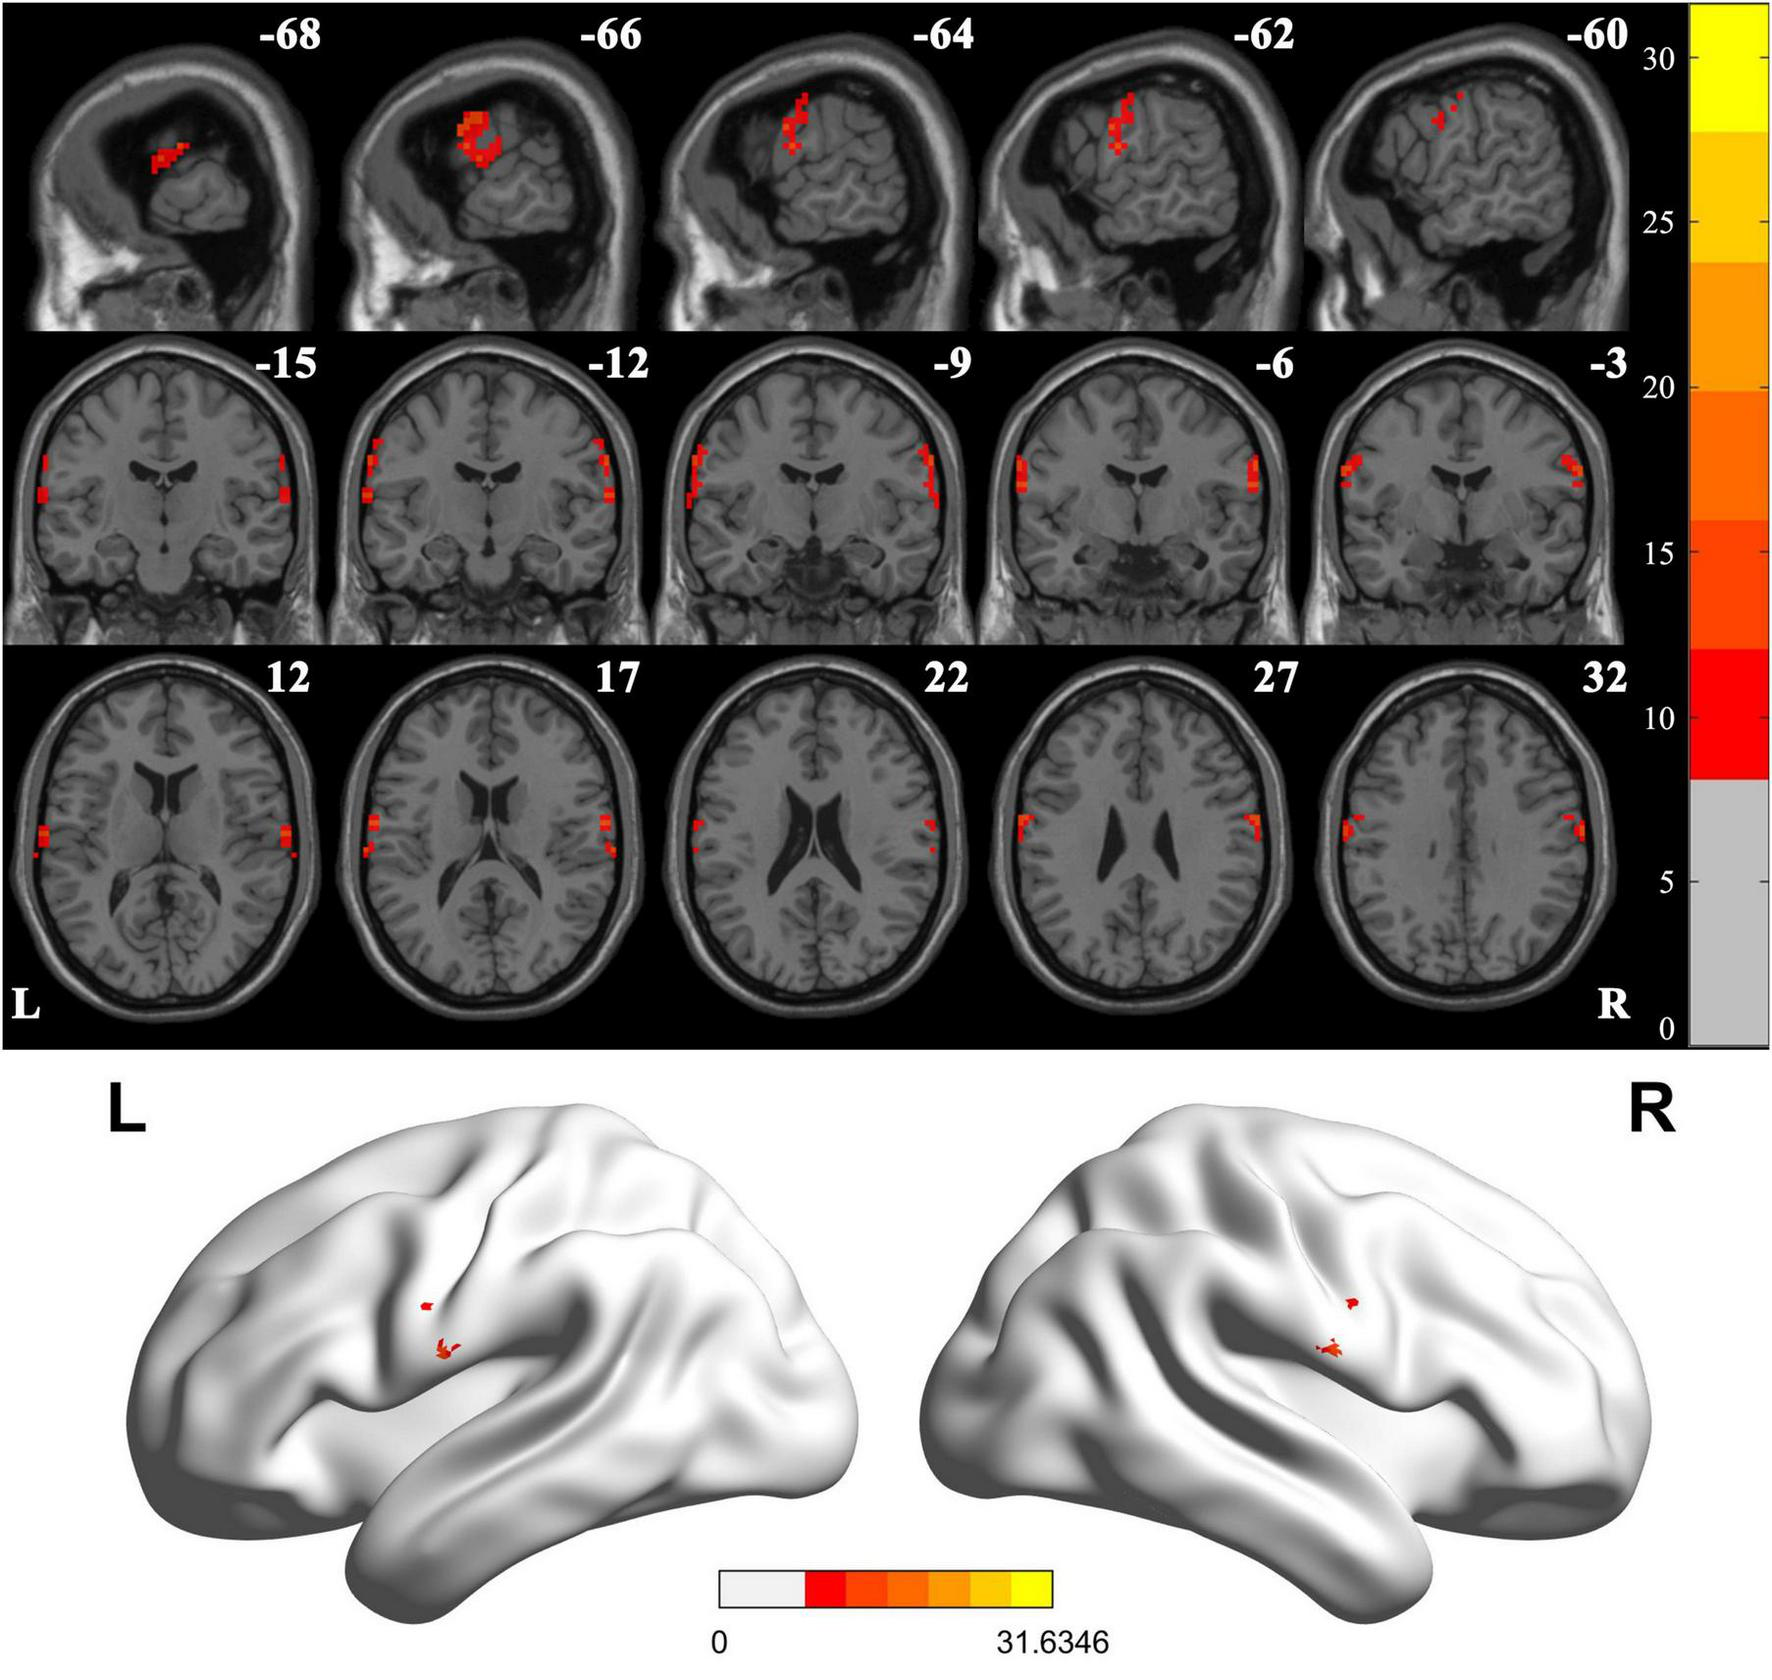

When comparing VMHC values in these three groups using one-way ANOVA, significant differences were detected in postcentral gyrus, extending to precentral gyrus (Figure 2 and Table 2; Voxel P < 0.001, Cluster P < 0.05, GRF correction) (Eklund et al., 2016). Post hoc analysis showed that in the pairwise ROI-based comparison, individuals with LBGIS and RBGIS exhibited reduced VMHC values compared to HC groups. There was no significant difference between the LBGIS and RBGIS groups (Figure 3 and Table 3).

FIGURE 2

www.frontiersin.org

Figure 2. Voxel-mirrored homotopic connectivity differences across groups. One-way analysis of variance shows brain regions with significant differences of the VMHC values across the three groups (corrected with GRF for multiple comparisons: voxel P < 0.001, cluster P < 0.05). GRF, Gaussian random field. L, Left; R, Right.